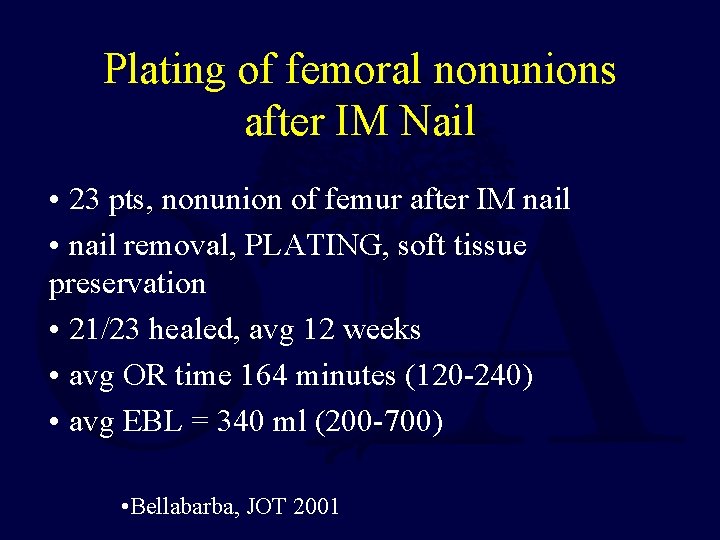

Plating of femoral nonunions after IM Nail • 23 pts, nonunion of femur after IM nail • nail removal, PLATING, soft tissue preservation • 21/23 healed, avg 12 weeks • avg OR time 164 minutes (120 -240) • avg EBL = 340 ml (200 -700) • Bellabarba, JOT 2001